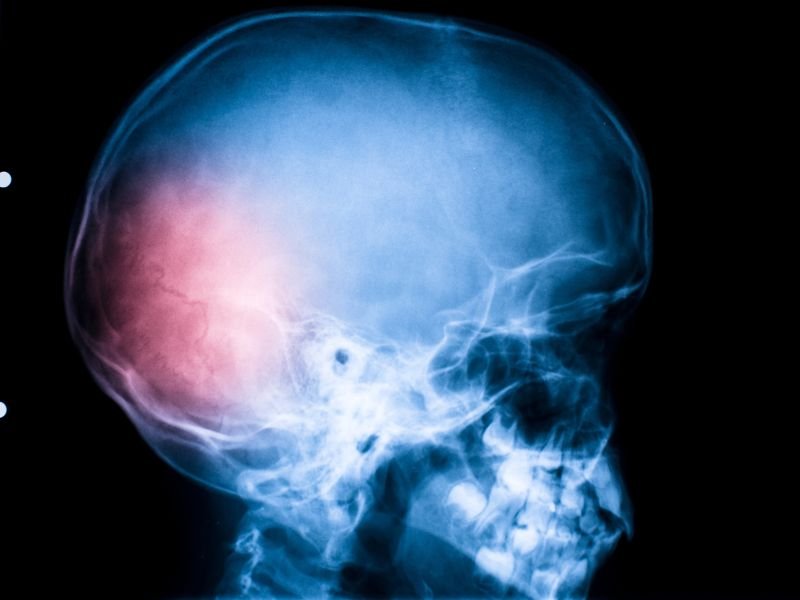

O traumatismo craniano é uma lesão causada por impactos diretos ou indiretos na cabeça. Pode variar desde traumas leves até quadros graves que exigem intervenção cirúrgica imediata. Essas lesões são comuns em acidentes de trânsito, quedas, agressões físicas ou esportes de alto impacto.

- Hematoma subdural ou epidural

- Hemorragia intracraniana

Quando há aumento da pressão intracraniana, hemorragias ou fraturas que comprimem estruturas cerebrais, a cirurgia é indicada.

- Hematoma epidural com desvio de linha média

- Hemorragia subdural aguda

- Hemorragias intracerebrais extensas

- Edema cerebral severo